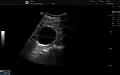

Renal ultrasonography of a simple renal cyst with posterior enhancement. -

Renal cyst as seen on abdominal ultrasound -